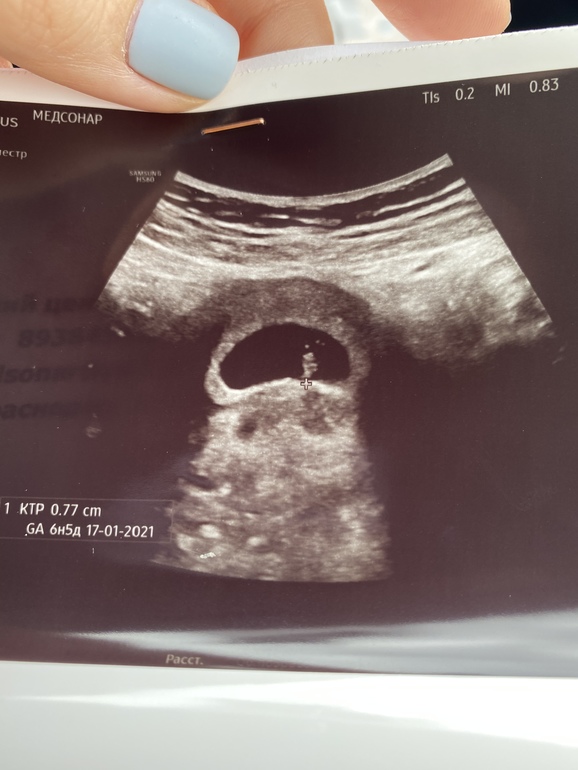

Результаты: УЗИ, КТГ, доплера, скринингаДевочки, была на первом УЗИ, всё хорошо, срок по месячным 7+4, по факту 6+3 из-за поздней овуляции, узи тоже 6+3 ставит.

Единственное что смутило узиста-гинеколога это сердцебиение , оно 110 ударов. Говорит не очень хорошее, может произойти зб 🤦🏼♀️ Через неделю повторить узи и если не увеличится надо идти к моему врачу за направлением на сохранение...спросила «может это из-за маленького срока», сказал «не влияет, мы на таком сроке от 130 намеряем»

UPD. Сделала узи через неделю, все отлично ) растём, сердцебиение 148 у/м мне кажется я на фото уже вижу зачатки ручек и ножек 😍❤️